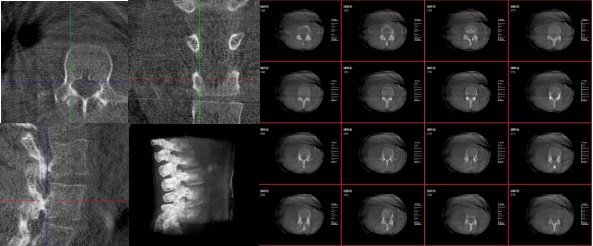

三維重建技術在醫學影像診斷領域十分重要,它是一種利用計算機軟件將二維醫學影像(如X光、CT、MRI等)轉化為三維立體圖像的技術,可以為醫生提供更直觀、更清晰的圖像信息,方便醫生從多個角度觀察病灶,從而更全面地了解病情,有助于提高診斷的準確性和效率。

1.診斷疾病:通過三維重建技術,醫生可以更直觀、清晰地觀察到患者體內的異常情況,如腫瘤、骨折等,從而更準確地診斷疾病。

2.手術規劃:在手術前,醫生可以通過三維重建技術對患者的病變部位進行詳細的觀察和分析,制定出最佳的手術方案。

3.手術導航:在手術過程中,醫生可以通過三維重建技術實時觀察手術器械的位置,提高手術的精確性和安全性。例如在關節外科手術中,存在植入物的錯位在術中不易發現的情況,如果在術后CT中檢查出,就不可避免地需要翻修手術,這就會增加并發癥的概率以及感染風險。而通過術中三維影像設備PLX C7600的檢查,可以立即發現植入物的錯位,減少不必要的第二次手術。